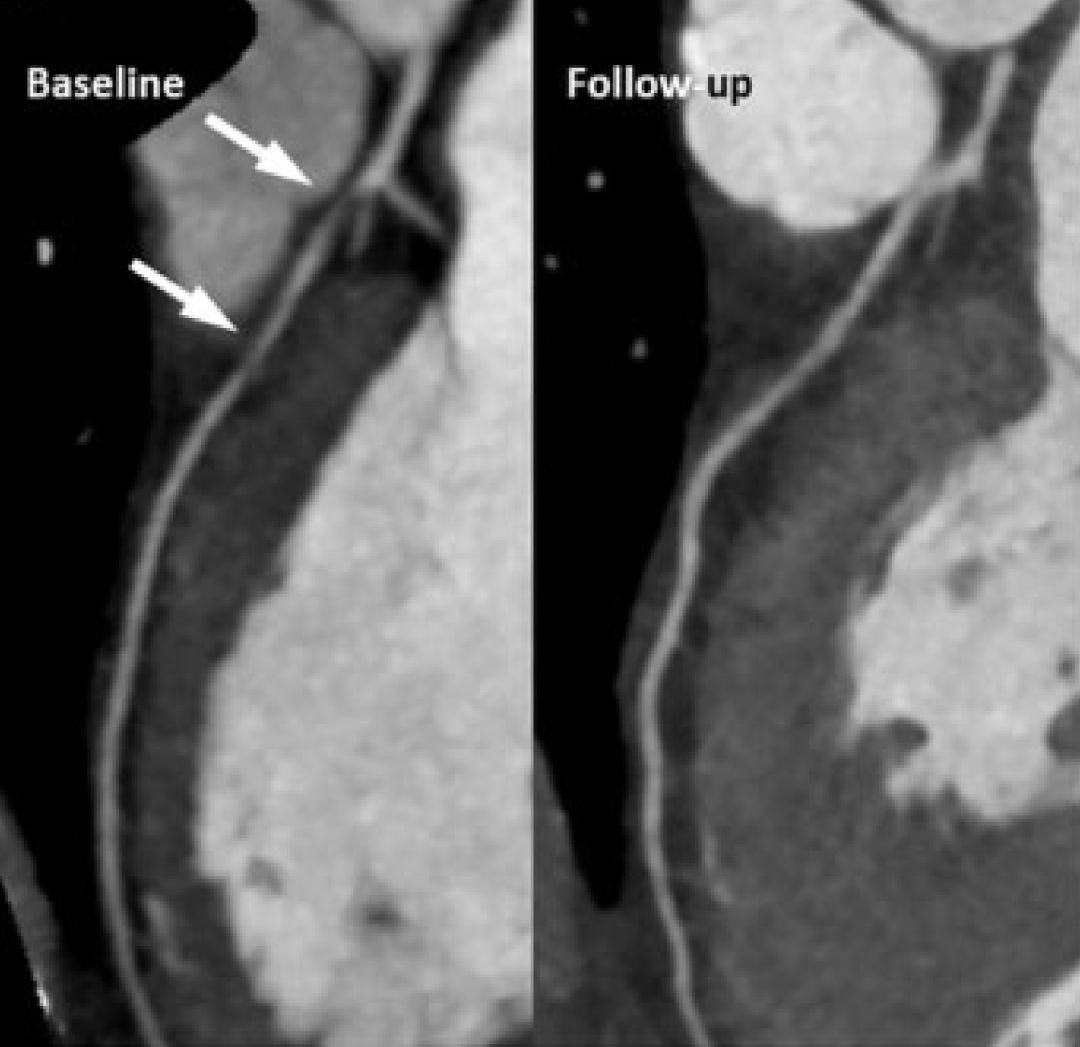

一位没有明确心血管危险因素的44岁中年女性,因“劳力性心绞痛2个月”就诊。为患者行冠脉CTA检查,发现LAD近端存在非钙化斑块,狭窄约70%,之后行核素检查确认LAD下游缺血。于是进行了冠脉造影,在LAD近端存在弥漫性中度狭窄,FFR为0.73。IVUS显示左主干与前降支弥漫斑块、负性重塑,最小管腔面积3mm2,斑块负荷55%。由于病变特点及患者个人意愿,并未进行介入治疗,维持了阿司匹林、地尔硫䓬、依折麦布+辛伐他汀治疗。

3年后为患者复查,惊奇地发现患者LAD下游缺血消失,行冠脉CTA显示斑块已经完全消退。

图1 LAD斑块完全消失